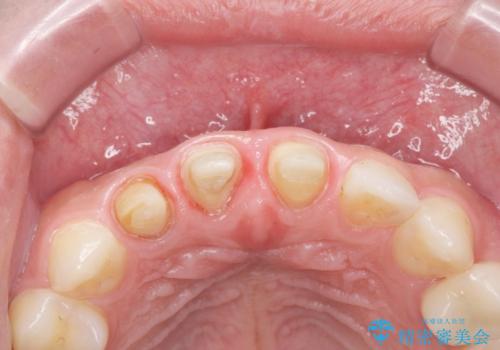

- 前歯(右上2)が黄色いとのことで来院。

レントゲンを撮ったところ前歯の被せ物が不適でした。

根管治療はご希望されなかったので(症状はなし)被せ物のやりかえ、右上2は被せ物の治療を行いました。